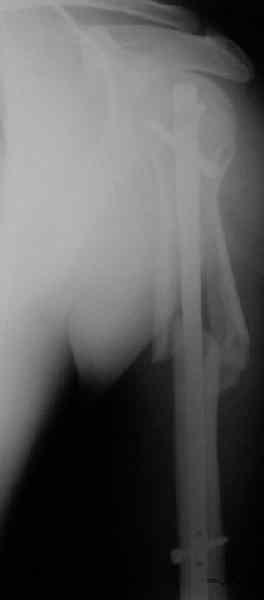

Попытка закрыто изменить положение не удалась. Передним доступом сделали открытую репозицию, гленоид без особенностей. Временно фиксировали спицами и остроконечным костедержателем. Фиксировали гвоздем T2 PHN (Stryker). Для профилактики вывихов после введения проксимальных винтов ротировали дистальный отдел кнаружи на 30

градусов как аналог остеотомии по Weber. Снимки в приложении. Комментарии и критика привествуются.

Attempt of closed reduction failed. Open reduction via anterior approach. The head was temporarily fixed by wires and sharp clamps. Fixation by a nail - T2 PHN (Stryker). The distal fragment has been rotated 30 degrees externally after proximal locking for dislocation prevention as "virtual" Weber osteotomy. Images attached.

Comments/critics are welcome.

To my mind it was most suitable for this injury because of long shaft extension.

> Is there only a single screw in the head?

All 3 screws are in the head. The feature of the nail is that it has four holes oriented not 45 degrees to frontal or sagittal planr, but anatomically to the head and both tubercles. The holes in the nail are threaded so angular stability is perfect, and contain a nylon bushing

preventing any screw rotation/back out.